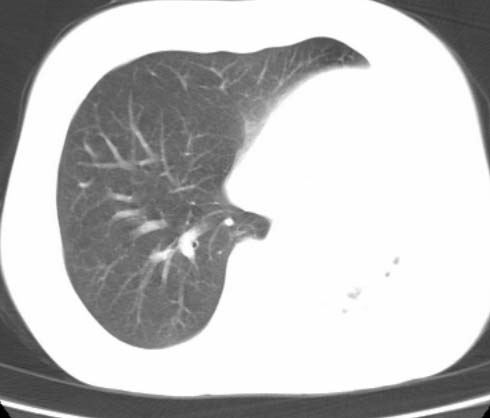

标题: CT25648:求教:是肺发育不全还是结核?

女  20岁。一月前咳血,诊“肺结核”抗痨治疗一月后,咳血停止,现复查。病人精神好。前后ct片对比未见明显变化。既往体检“正常”

1)考虑左肺结核并肺不张、支气管扩张。2)纵隔疝。

考虑左肺结核,左肺毁损,纵膈左偏,既往体检正常不可靠,tb一个月也不会这个样子的,有钙化,应该病程较长,冰冻三尺非一日之寒!

左肺发育不全。